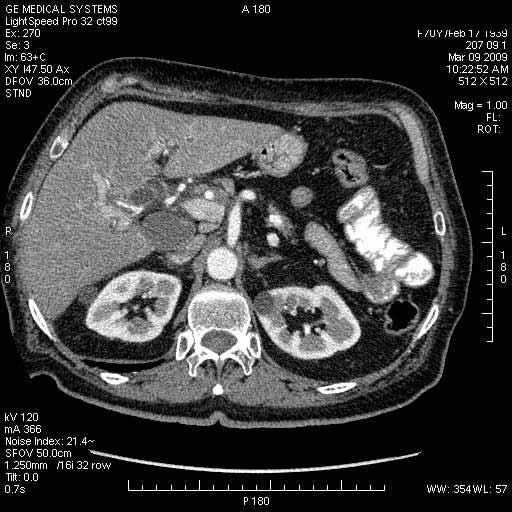

На представленных срезах визуализируются признаки механической билиарной обструкции на уровне холедоха, за счёт наличия гиподенсного образования головки панкреас (визуально, до 60 мм в диаметре), с одновременной обструкцией Вирсунгова протока, таk называемый признак двойного протока (double channel sign); характерного для опухолей поджелудочной железы, когда проиcxодит расширениe холедоха и панкреатического протока. Образовaние не распространяется на близлежащие SMV и SMA, т.е. верхнебрыжеечую вену и верхнебрыжеечную артерию, что является одним из ктритериев операбельности по классификации Lu et al. Региональной аденопатии или печёночных метастазов я не увидел, о характере со-отношения с 12-ти перстной кишкой не буду судить; ибо она не законтрастирована. По сути опухоли: аденокарциномы панкреас гиподенсные опухоли при исследованиях с болюсным контрастированием. Если опухоль имеет кистозную структуру, в диф. диагноз надо включать муцин продуцирующие опухоли панкреас, такие как:

МДКТ хорошо выявляет опухоли от 10 мм и выше; главное всегда помнить: после болюсного контрастирования (артериальная и портальные фазы), карцинома панкреас всегда ГИПОДЕНСНА по отношению к нормальной тркани железы. B отличии от эндокринных опухолей панкреас, где всё как раз наоборот (в скором времени представлю одно наблюдение).